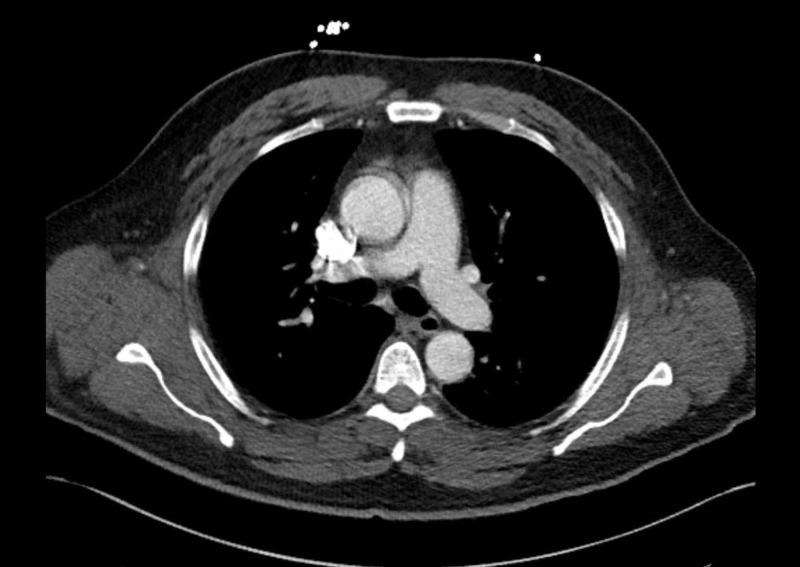

奥美拉唑起始治疗后表现为横纹肌溶解的多发性肌炎

Polymyositis Presenting as Rhabdomyolysis After the Initiation of Omeprazole.

Rhabdomyolysis is a clinical syndrome with a wide range of presentations; it results in muscle necrosis and release of intracellular muscle contents into the circulation. Inflammatory myopathies are a rare cause of rhabdomyolysis. We present a case of a 46-year-old male with a two-week history of progressively worsening diffuse muscle pain after he had been prescribed omeprazole one month prior. A creatine phosphokinase (CPK) elevation was noted, which persisted despite treatment with IV fluids, sodium bicarbonate, and close correction of electrolytes. Further workup, including autoimmune and infectious etiologies, was notable for elevated antinuclear antibodies (ANA), erythrocyte sedimentation rate (ESR), and C-reactive protein (CRP). Furthermore, a muscle biopsy showed evidence of endomysial inflammatory cells, consistent with a diagnosis of polymyositis. Steroids were initiated with significant improvement in symptoms and a decrease in CPK levels. The patient was discharged on a tapering dose of steroids and, on follow-up with the rheumatologist, transitioned to methotrexate with control of symptoms. In patients with rhabdomyolysis who do not respond to first-line therapy, obtaining a detailed medication history and screening with ANA and ESR are encouraged. Given the link between medication and autoimmune disease, clinicians should consider autoimmune myopathy in the differential for cases with persistently elevated creatine kinase. Prompt diagnosis with early initiation of immunosuppressive medication may improve outcomes and avoid complications associated with untreated rhabdomyolysis or polymyositis.

摘要